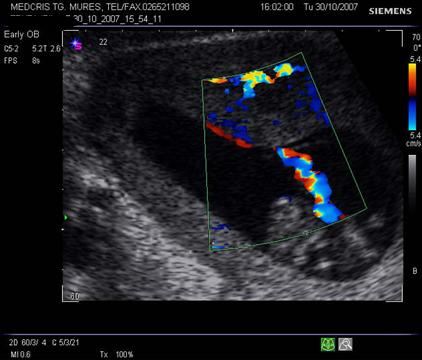

Fig. nr.222. Hematom

la nivelul placii deciduale a

placentatiei la 10 sapt. , cu intreruperea vascularizatiei la Doppler color (

sageata ). Se remarca vascularizatia cordonului ombilical si insertia centrala

a acestuia in placenta